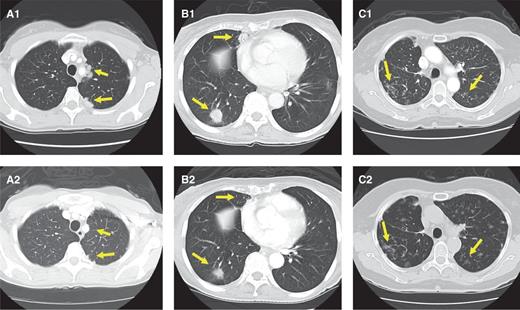

A1, baseline chest CT of the first patient with TRIM33–RET showing paramediastinal and pleural-based nodularities in the left upper lobe. A2, repeat imaging after 4 weeks of therapy revealing the disappearance of paramediastinal disease and a significant reduction of pleural-based disease. B1, chest CT of the second RET fusion-positive patient showing 2 nodules in the right lower lobe. B2, decrease in both size and solid components of both lesions at 4 weeks. C1, baseline imaging of the third patient with KIF5B–RET showing small bilateral pulmonary nodules. C2, stable disease at 4 weeks. All responses have been confirmed at 12 weeks and have since been maintained clinically and radiographically. Baseline disease burden was relatively low for all 3 cases.

The patient was enrolled in our phase II study of cabozantinib after progression on 2 prior lines of therapy. Cycle 1 toxicities included grade 2 dysgeusia and grade 1 mucositis, diarrhea, and fatigue; subclinical hypothyroidism was managed with thyroid hormone replacement. Follow-up imaging conducted after 4 and 12 weeks of therapy revealed a confirmed partial response with a 66% decrease in measurable disease in the lungs and pleura by Response Evaluation Criteria in Solid Tumors (RECIST) v1.1 (Fig. 2A). A follow-up ophthalmologic examination revealed partial regression of the patient's bilateral retinal metastases along with resolution of episodic mild blurring of vision. Although sclerotic areas of bony metastasis to the upper sacrum and posterior right ilium were not measurable by RECIST, treatment was accompanied by a clinical response to therapy with the disappearance of tumor-related sacral pain. The patient was not previously treated with a bisphosphonate or anti-RANK ligand therapy. She has been on trial now for 5 months (20 weeks) and remains progression-free and on active therapy.

The second patient was a 75-year-old African-American female never-smoker who was RET fusion-positive by FISH and reverse transcriptase PCR (RT-PCR) for KIF5B–RET. She was initially treated with sequential chemotherapy and radiation for unresectable stage IIIA (T4N1M0) poorly differentiated lung adenocarcinoma. She was subsequently found to have recurrent, metastatic disease, as evidenced by the development of enlarging bilateral pulmonary nodules in the absence of distant disease. She was treated with cabozantinib on-protocol. Cycle 1 toxicities included grade 3 fatigue requiring cabozantinib dose reduction to 40 mg/day and grade 1 transaminase elevation. Grade 3 proteinuria was a late toxicity requiring further dose reduction to 20 mg/day. Despite the need for dose reductions, the patient had clinical improvement in cough and shortness of breath and a partial response to therapy at 4 weeks (Fig. 2B). This was confirmed at 12 weeks with a decrease in disease burden by 32% by RECIST v1.1. The patient remains progression-free on therapy at 4 months (16 weeks).

The third patient was a 68-year-old Caucasian female never-smoker positive for a RET fusion by FISH. She initially underwent a right upper lobectomy for a stage I lung adenocarcinoma. She was thereafter found to have metastatic mixed-subtype adenocarcinoma (predominantly papillary with lepidic and solid patterns) with multiple bilateral pulmonary nodules and no evidence of distant disease. She began treatment with cabozantinib after progression of disease on first-line chemotherapy. Cycle 1 toxicities included grade 3 hypertension requiring dose reduction to 40 mg/day of cabozantinib, grade 2 fatigue, and grade 1 skin toxicity. At 4 weeks on-study, she was noted to have stable disease (Fig. 2C) that has since been maintained clinically and radiographically approaching 8 months (31 weeks) into treatment.